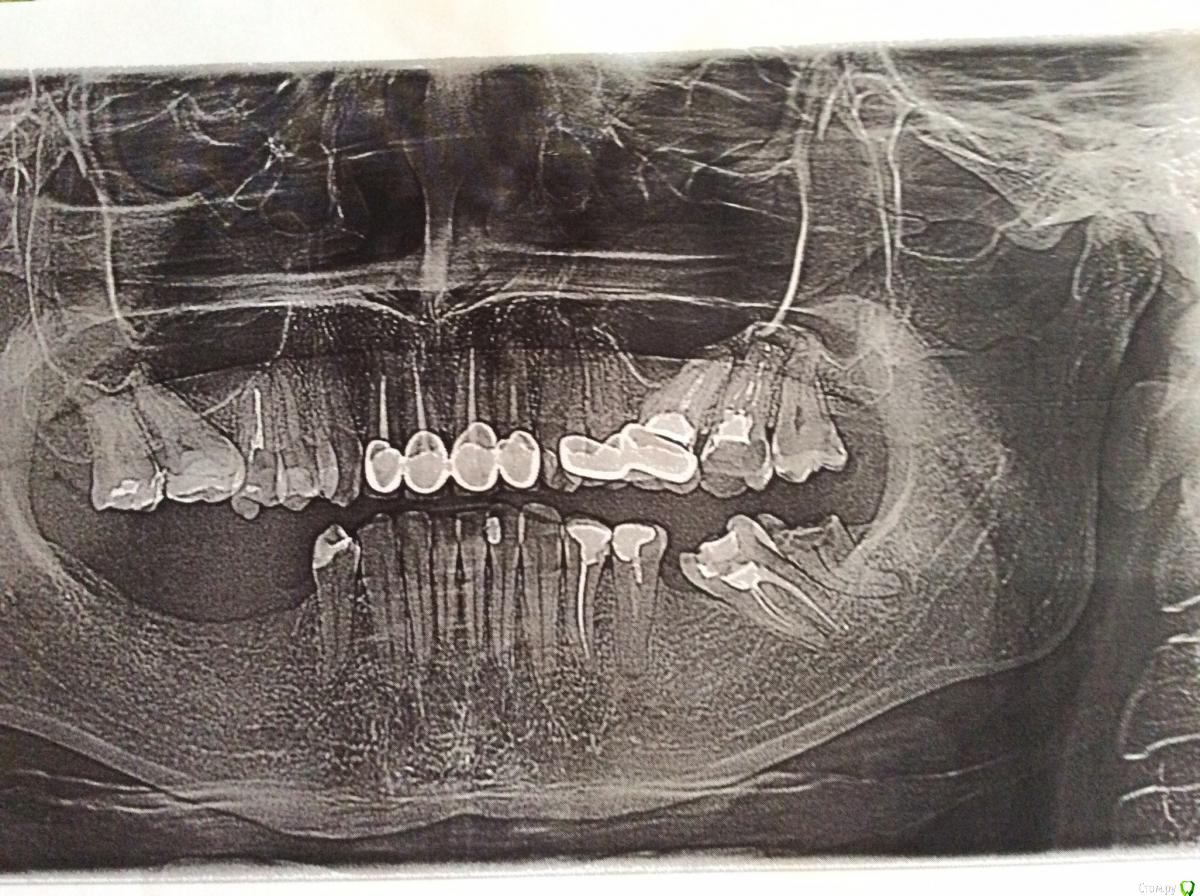

Kolanhoe23 Опубликовано 29 июля, 2015 Поделиться Опубликовано 29 июля, 2015 Мне 30 лет. Сходила на консультацию в 2 клиники, говорят практически противоположные вещи. В одной сказали, что вниз нужно ставить как минимум 5 имплатнов, в другой говорят, что можно обойтись и 3. Один врач сказал, что верхние коронки нужно обязательно снимать, что с левой стороны сильный артроз еще чуть-чуть и пойдет воспаление в мозг. другой вообще по этому поводу ничего не сказал. Снимки прилагаю. Буду очень благодарна за консультацию. 1 Ссылка на комментарий

faity Опубликовано 29 июля, 2015 Поделиться Опубликовано 29 июля, 2015 здравствуйте, давайте сразу определимся, я человек не добрый и радикальный, но (хочется верить) эффективный 1.8, 1.7, 2.6, 2.7, 2.8, 3.8, 3.7 под снос1.6, 1.7, 2.5-2.7, 3.6, 3.7, 4.5-4.7 импланты с мостами, а в идеале одиночные импланты, плюс 2-хсторонний синус лифтинг и скорее всего Направленная Костная Регенерация в области нижней челюсти мой план лечения даст вам гарантированный результат на долгие годы, но можно и полумеры попробовать, непрогнозируемо... Ссылка на комментарий